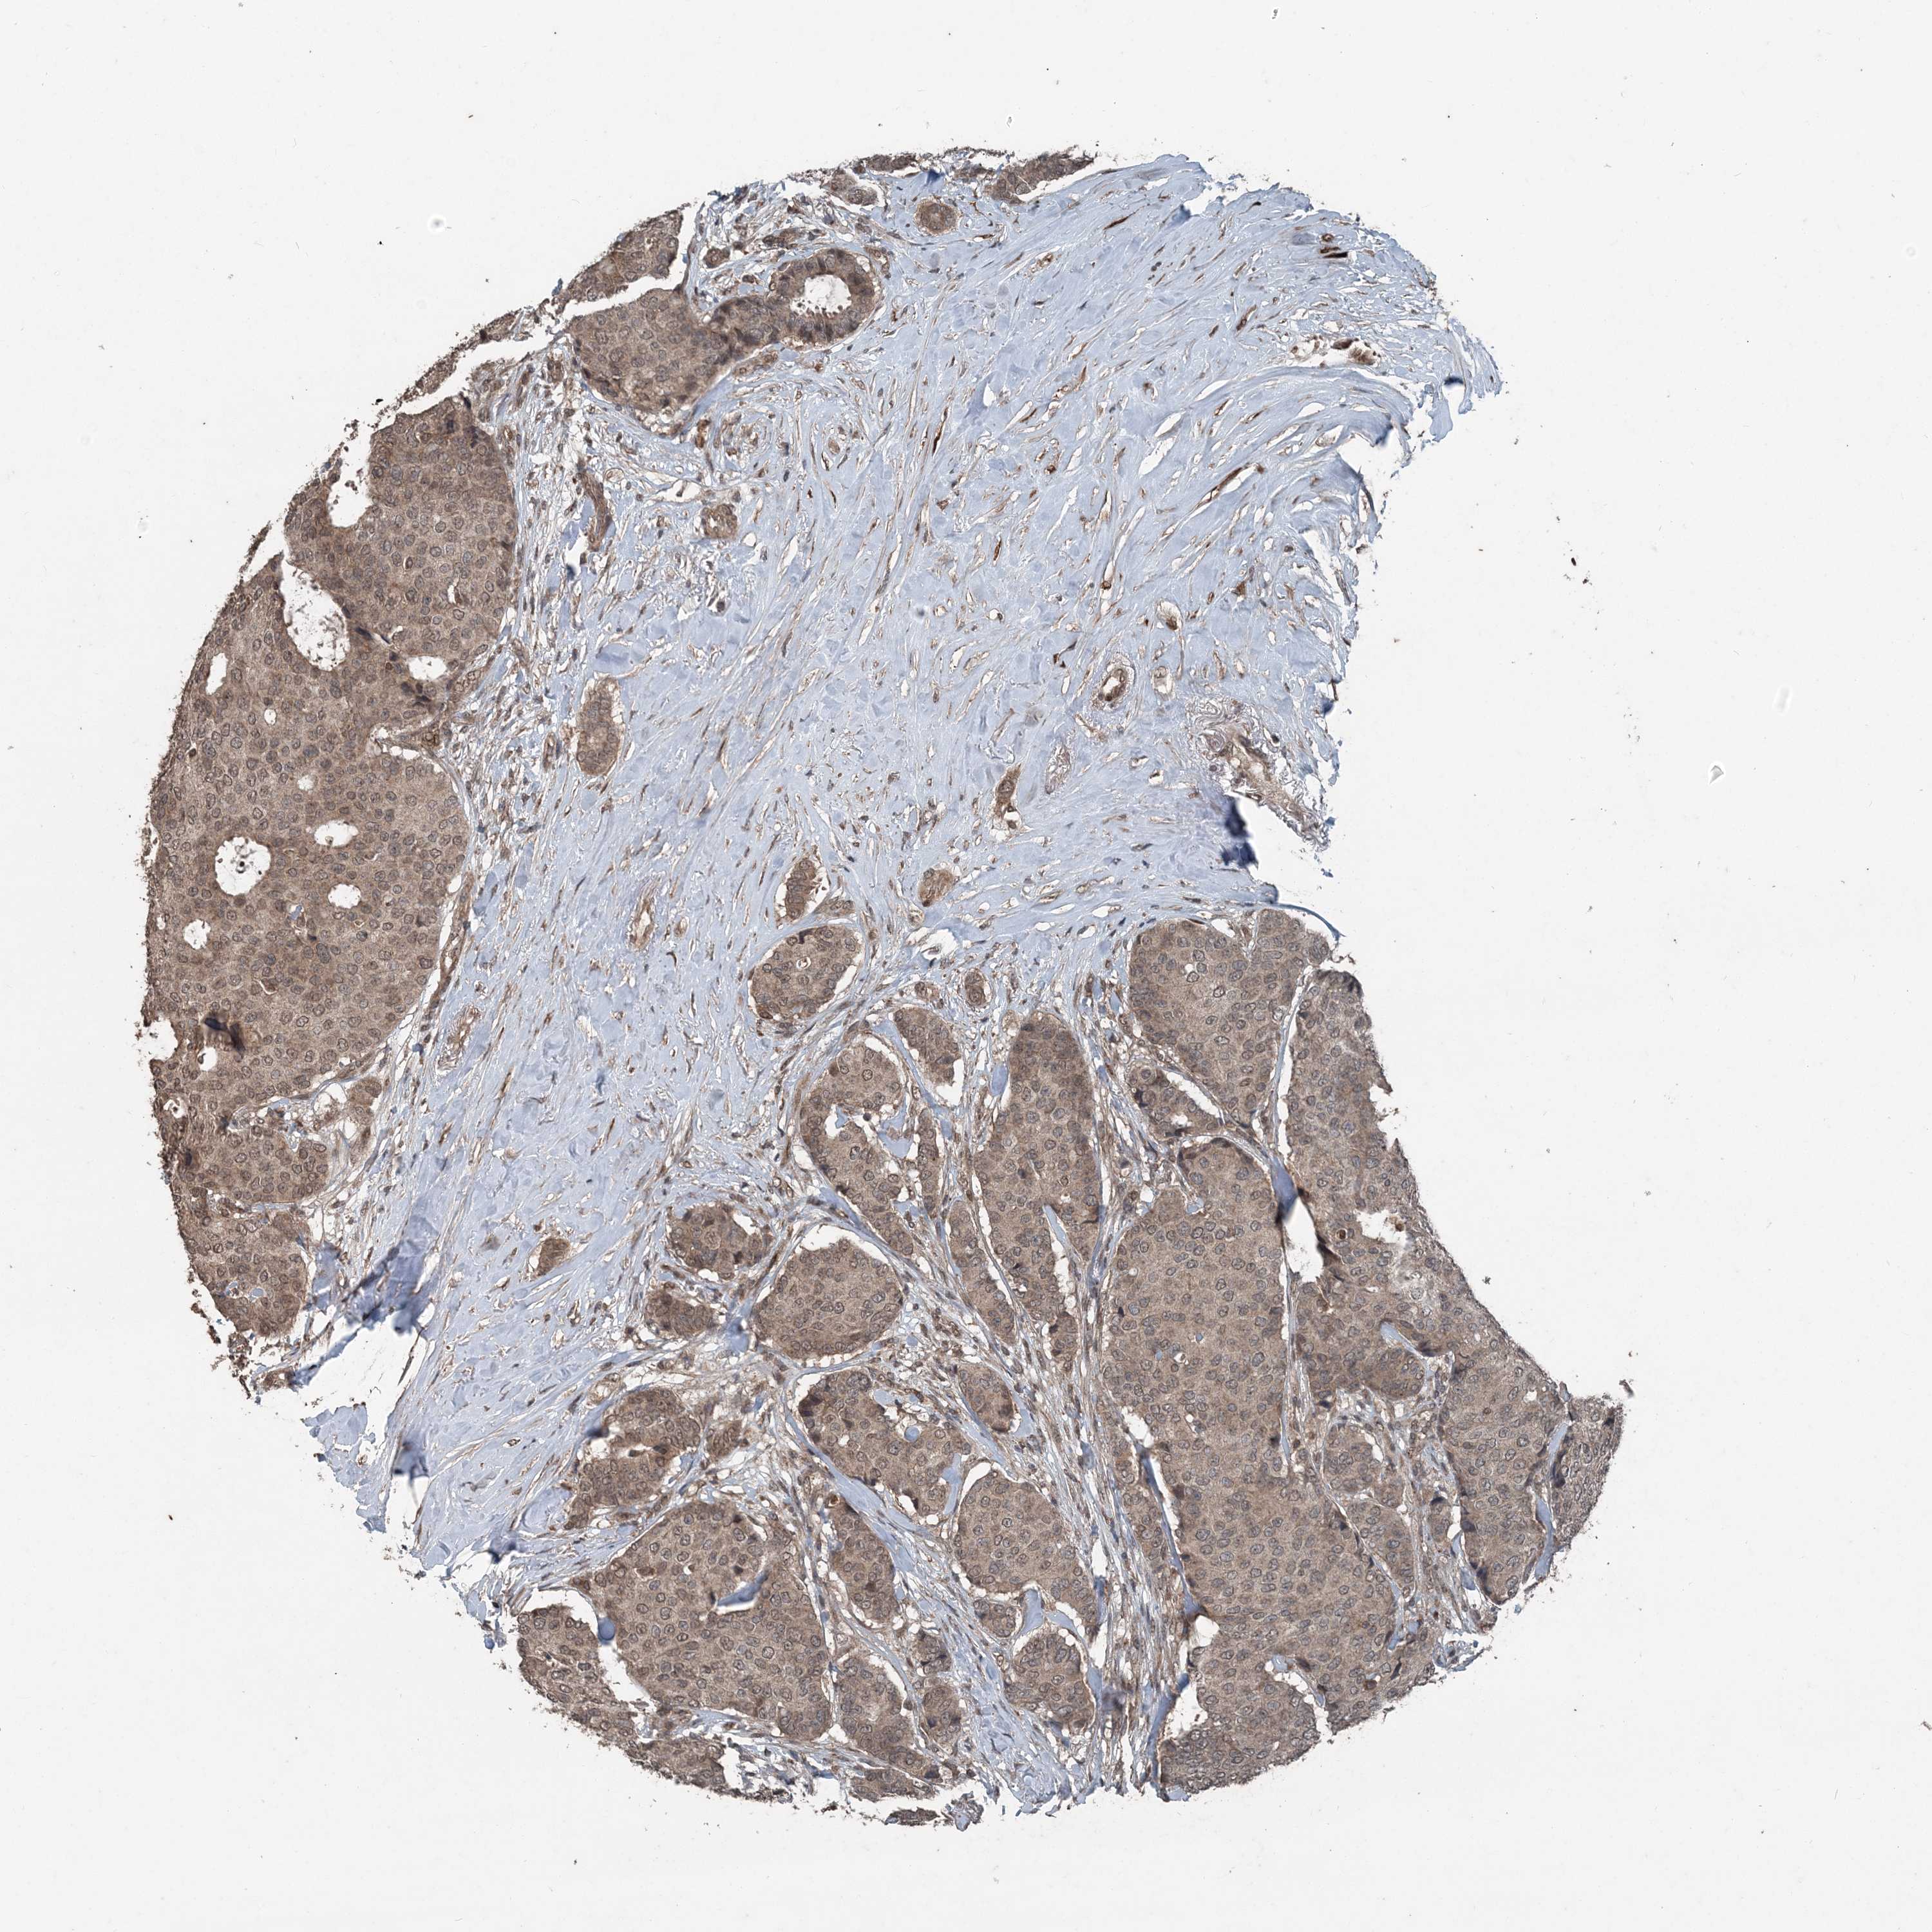

CANCER BREAST CANCER Show tissue menu

BRCA TCGA BRCA VALIDATION PROTEIN EXPRESSION

ANTIBODIES

AND

VALIDATION